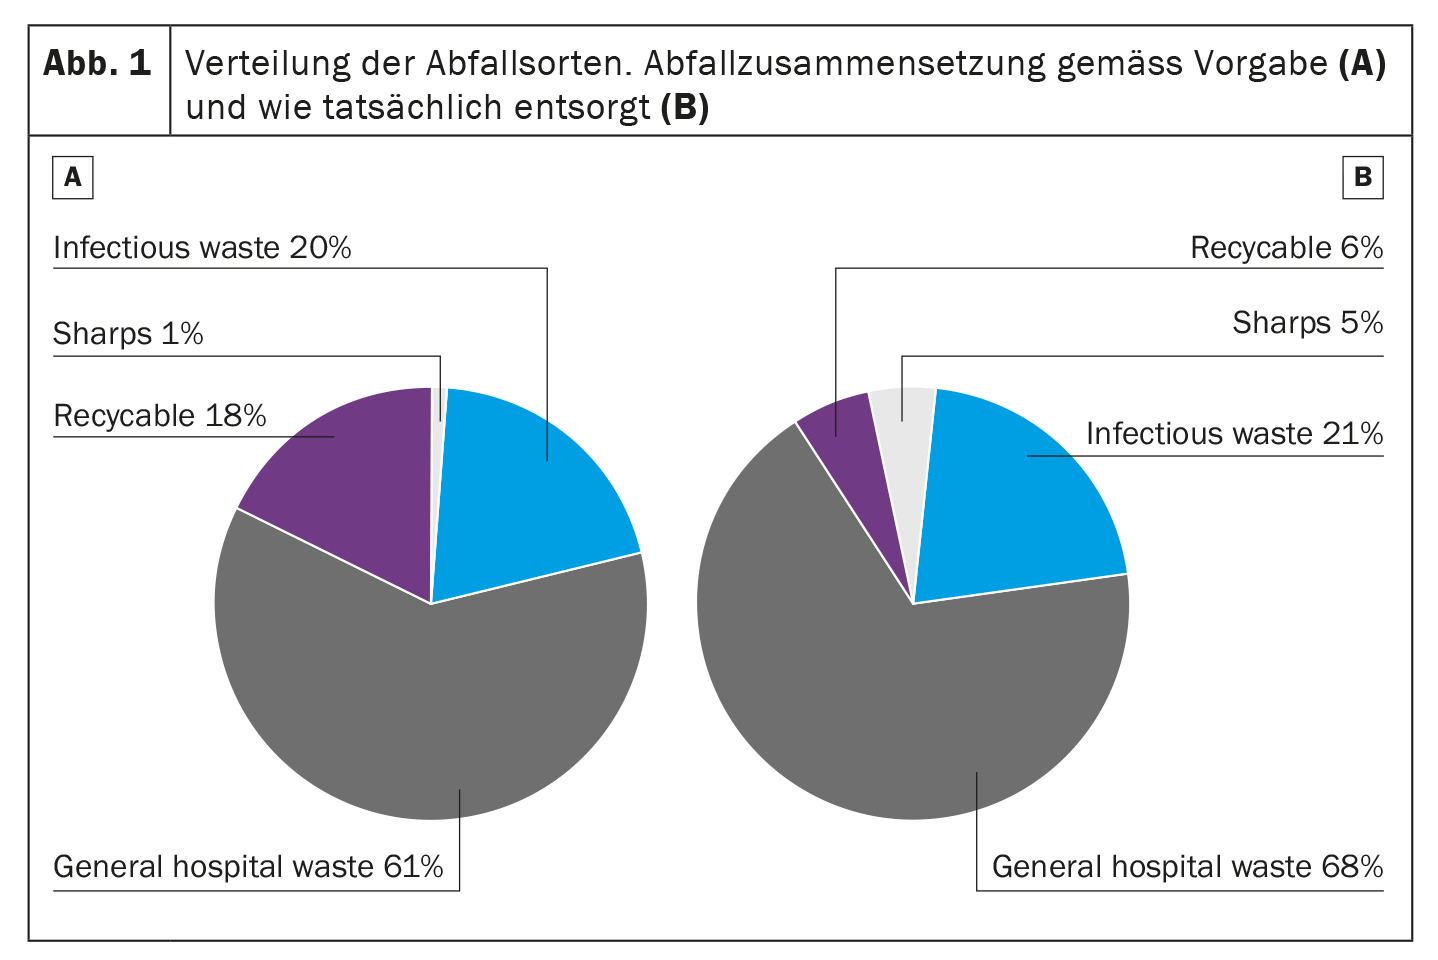

The waste composition is mainly general hospital waste (61%), which also has to be incinerated in Switzerland. 18% of the waste is considered recyclable, e.g. plastic, 20% was infectious waste – mainly suction fluids. Sharp objects accounted for only 1% (Fig. 1A). Thus the theory. “However, if we look at how our waste is actually disposed of, the picture is slightly different,” said the researcher: “Only a third of recyclable waste is actually recycled in our department (6%) – this is mainly glass and some paper.” In addition, sharp objects, e.g. permanently installed disposable tips, are not actually sharp objects in the sense of the regulation. The actual proportion was therefore 5% (Fig. 1B).

The proportion of leftovers, such as unused endoscopy kit components or syringes filled with water/Nacl, was also striking. Rybinski and his colleagues wondered what potential for reduction there would be in the department if the waste were disposed of differently. “For example, if we could recycle plastics such as O2 tubing, packaging and crystalloid containers, we would produce 17% less general waste.”